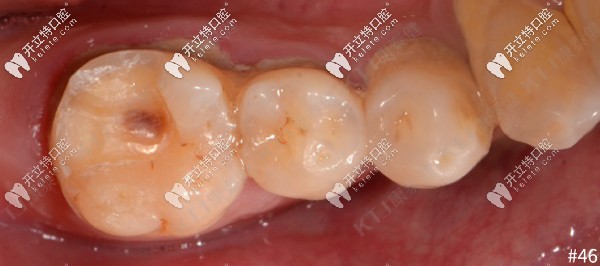

牙齒癥狀:36、46牙體缺損未及髓腔,根尖周未見(jiàn)低密度影像

46牙齒缺損檢查